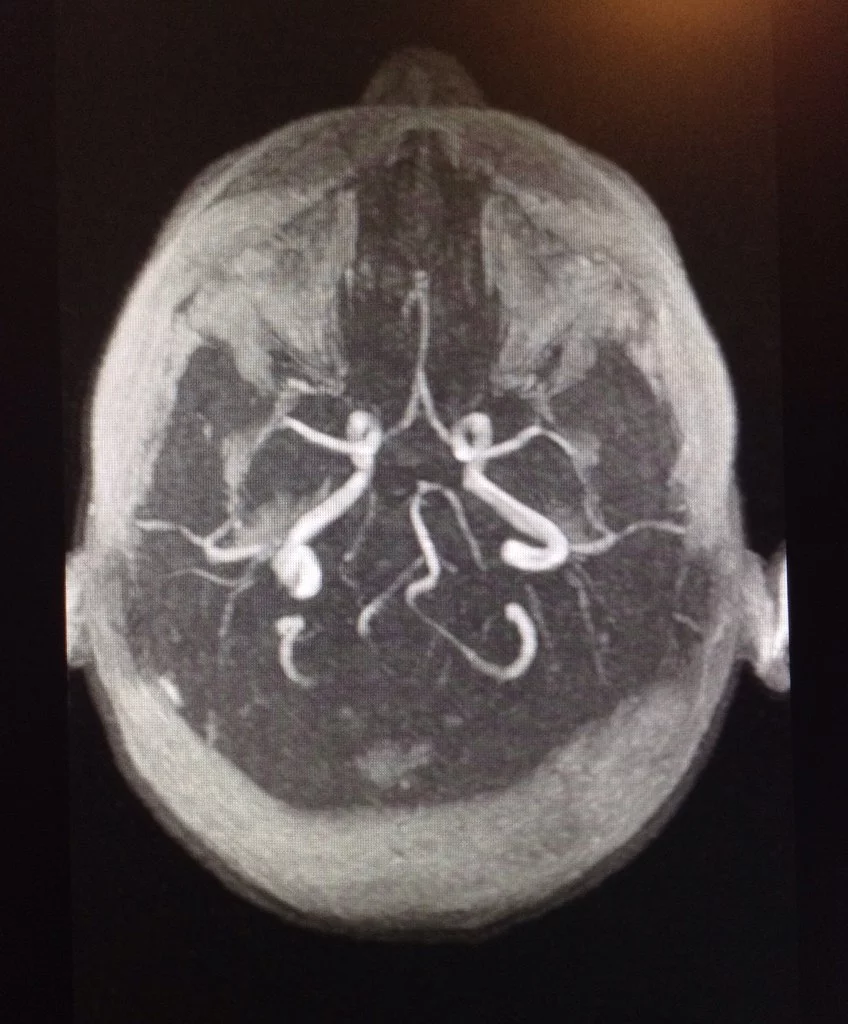

Внимание! У родной сестры нашего побратима

случилась беда. В головном мозгу образовался кровяной сгусток (в виде петли), который блокирует кровеносный сосуд и кровь дальше не проходит, в обескровленном участке мозга нервные клетки начинают отмирать, и развивается некроз тканей. Сейчас она находится в больнице, отделение нейрохирургии. Требуются постоянные МРТ головного мозга (магнитно-резонансная томография), консультация у нейрохирурга в Киеве и лечение. Просим помощи! Нужны деньги на лечение! Карта Приват банка 5168 7553 9987 6032 Киселёв Данил Алексеевич